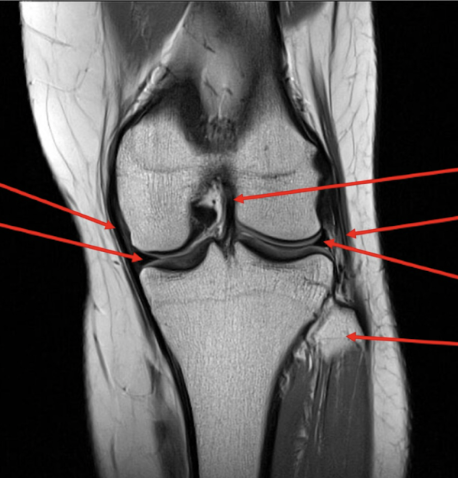

label each

2- lateral and medial condyles of femur

4- vastus lateralis muscle

5-posterior cruciate ligament

6- anterior cruciate ligament

7- medial meniscus of knee

8- lateral meniscus of knee

9-tibia

10-fibula